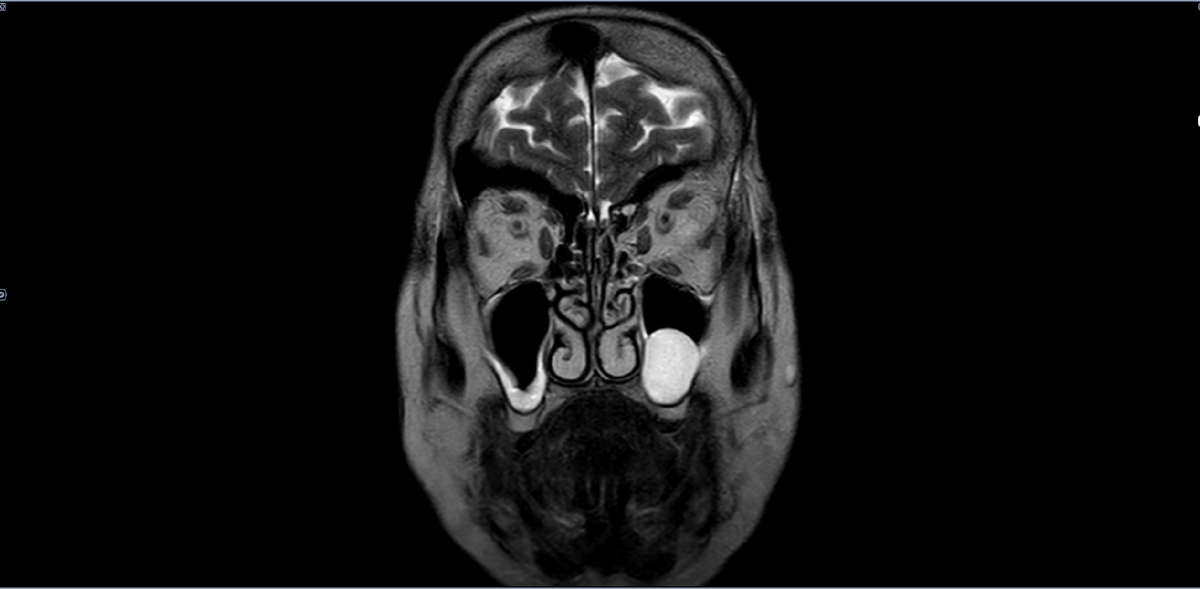

МРТ-киста верхнечелюстной пазухи

В нижней стенке левой в/ч пазухи визуализируется киста размером 24х16мм,гомогенного гиперинтенсивного МР-сигнала на Т2, с четким полуокруглым контуром. Утолщение слизистой правой в/ч пазухи.

Категория годности по ст.10(Доброкачественные новообразования (кроме доброкачественных новообразований нервной системы и мозговых оболочек), новообразования in situ:),в-А2(годен к в/сл.),также при данном заболевании может использоваться статья 49в-Б3(годен к в/сл. с незначительными ограничениями),при наличии вышеописанных жалоб, без наличия значительных осложнений(нагноение кисты) .